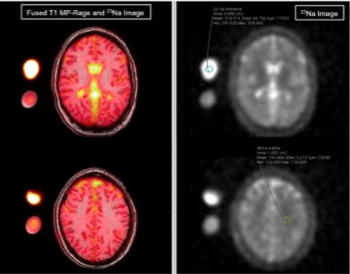

Dr. Meyer and colleagues explored a magnetic resonance technique called cerebral sodium MRI as a possible means to help in the diagnosis and understanding of migraines. While MRI most often relies on protons to generate an image, sodium can be visualized as well. Research has shown that sodium plays an important role in brain chemistry.

Figure 1. MR image examples of a migraine patient with exemplary region-of-interest placement in an external sodium reference phantom and in the white matter (right image). Left: Fused T1-MP-Rage and sodium image; right: sodium image